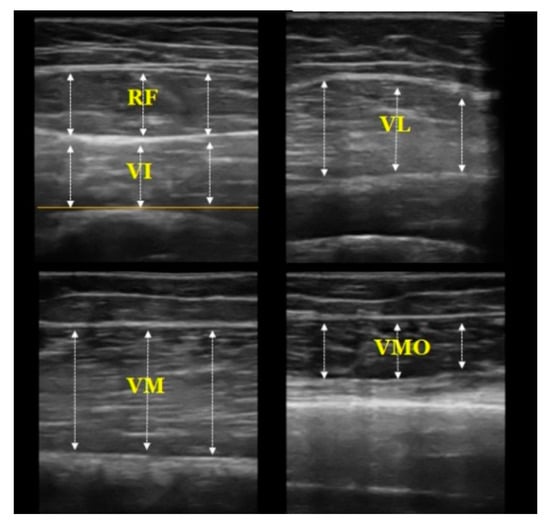

2.3.2. Muscle Thickness Measurement

| RF | Rectus Femoris | VI | Vastus Intermedius |

| VL | Vastus Lateralis | VM | Vastus Medialis |

| VMO | Vastus Medialis Obliques | ||